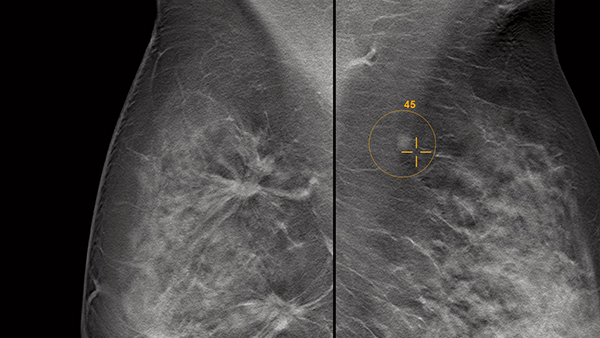

AI解析ソフトウエアを搭載したsyngo. Breast Careは,病変をROIで囲み,悪性度をスコア化して表示することが可能で,2Dだけでなくトモシンセシスのスライス画像にも対応する。併せて,マンモグラフィの稼働率管理や業務効率向上をサポートする「teamplay Mammo Dashboard」も紹介した。

AI技術で病変をROIで囲み悪性度をスコア化する「syngo. Breast Care」(薬機法未承認)